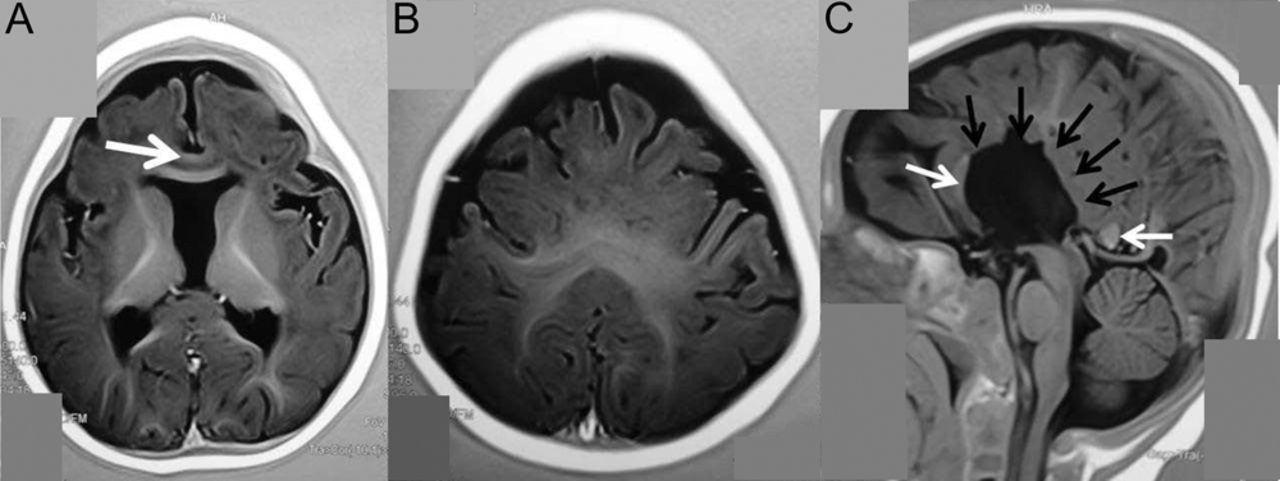

图

Syntelencephaly: MRI出现

轴t1反转恢复序列(IR)的融合显示缺乏透明隔扣带回(白色箭头)(A)和连续白质两半球间的中间的部分地区(B)。矢状t1红外序列(C)没有中体胼胝体(黑色箭头)和膝和压部(白色箭头)。

Syntelencephaly,前脑无裂畸形的一种独特的子集,1是一种罕见的大脑半球的畸形融合不会发生在吻侧前脑而是后额地区;因此,替代术语“中间两半球间的融合”或“背叶的前脑无裂畸形。“临床表现各不相同,有精神缺陷或全球普遍发育迟缓。2在所有情况下的透明隔缺席。通常与经典的前脑无裂畸形,胼胝体的中间体是缺乏这种障碍。